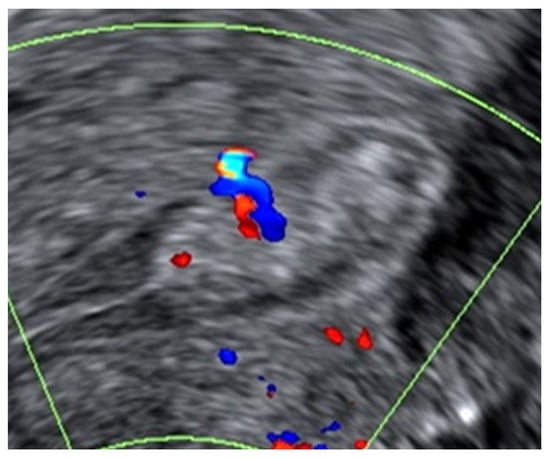

- Timmerman, D.; Verguts, J.; Konstantinovic, M.L.; Moerman, P.; Van Schoubroeck, D.; Deprest, J.; Van Huffel, S. The pedicle artery sign based on sonography with color Doppler imaging can replace second-stage tests in women with abnormal vaginal bleeding. Ultrasound Obstet. Gynecol. 2003, 22, 166–171. [Google Scholar] [CrossRef]

| Presence of a pedicle vessel b | 92 (41.4) | 12 (66.7) | n/a | 0.048 d |